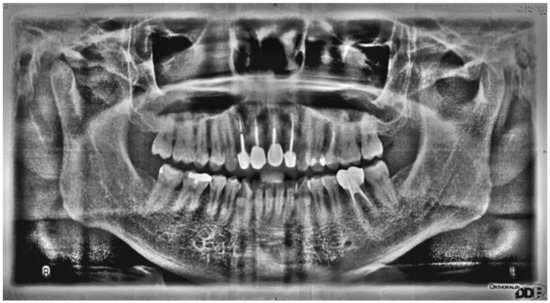

Tooth Position Determination by Automatic Cutting and Marking of Dental Panoramic X-ray Film in Medical Image Processing

2. Method

3. Results